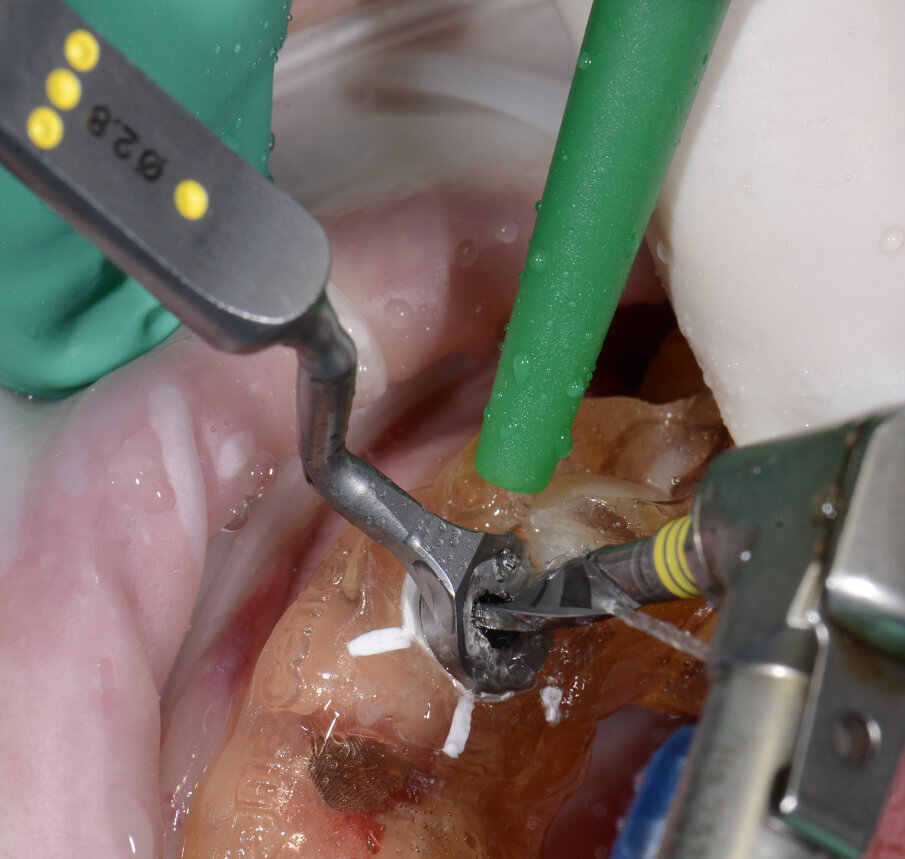

Il nostro obiettivo è quello di riuscire a dare alla paziente un provvisorio immediato nell’arco di due ore. Questo diventa possibile perché abbiamo utilizzato un flusso digitale fin dall’inizio. In laboratorio vengono realizzate la dima chirurgica (Figg. 16, 17), la dima protesica (Fig. 18) e anche il provvisorio (Figg. 19-21) che contiene delle alette di riposizionamento. Il tutto gestito con modelli digitali sui quali saremo in grado di funzionalizzare il provvisorio post-chirurgico (tecnica DIL). In un caso come questo se utilizziamo un flusso digitale possiamo evitare subito dopo la chirurgia di rilevare un’impronta degli impianti inseriti. Infatti, utilizziamo una dima chirurgica che ci faciliterà le fasi di intervento. La dima ci consentirà di non fare lembi e nessuna incisione di rilascio (Fig. 22), dopo aver inserito gli impianti (BLX Straumann) (Figg. 23-31) e aver controllato il loro alloggiamento, inseriamo sugli stessi dei transfert da impronta (Fig. 32).

Fig. 25 - Preparazione letto implantare.

Alloggiamo la dima protesica (Fig. 33), e blocchiamo i transfert con della resina trasparente (tecnica DIL) (Figg. 34, 35). In questo modo possiamo far riposare il paziente in studio dopo appena 35 minuti dall’inizio dell’intervento. La dima protesica, infatti (Fig. 36) con i transfert inseriti viene completata con l’unione degli analoghi ai transfert (Fig. 37). L’insieme così composto viene riadattato sul modello master digitale iniziale (Figg. 38-40) sul quale era stata costruita sia la dima chirurgica che la dima protesica come anche il provvisorio. Gli analoghi vengono bloccati sul modello con resina trasparente (Figg. 41-43). Alloggiamo il provvisorio sul modello master digitale così ottenuto (Figg. 44, 45).

Il piano di trattamento prevede l’estrazione degli elementi dentali, l’inserimento di due impianti e la realizzazione di una protesi fissa di quattro elementi. Il problema da gestire è quello della fase provvisoria. Non è ipotizzabile una protesi mobile e quindi programmiamo di inserire subito dopo l’intervento un provvisorio immediato. Questo ci consente di condizionare da subito i tessuti periimplantari e anche le zone dei ponti. Si rileva un’impronta digitale (Figg. 5, 6), e la programmazione degli impianti viene effettuata con un software di chirurgia guidata (Fig. 7) e la posizione degli impianti nello spazio biologico e nello spazio protesico viene fatta sulla base di una ceratura diagnostica (Figg. 8, 9). Inseriamo gli impianti virtuali nell’osso disponibile (Figg. 10-13) e in relazione all’aspetto protesico correggiamo l’asse di inclinazione degli impianti con componenti secondarie angolate a 17° (Figg. 14, 15). Questo ci consentirà di realizzare una protesi avvitata con i fori situati nella zona palatale.